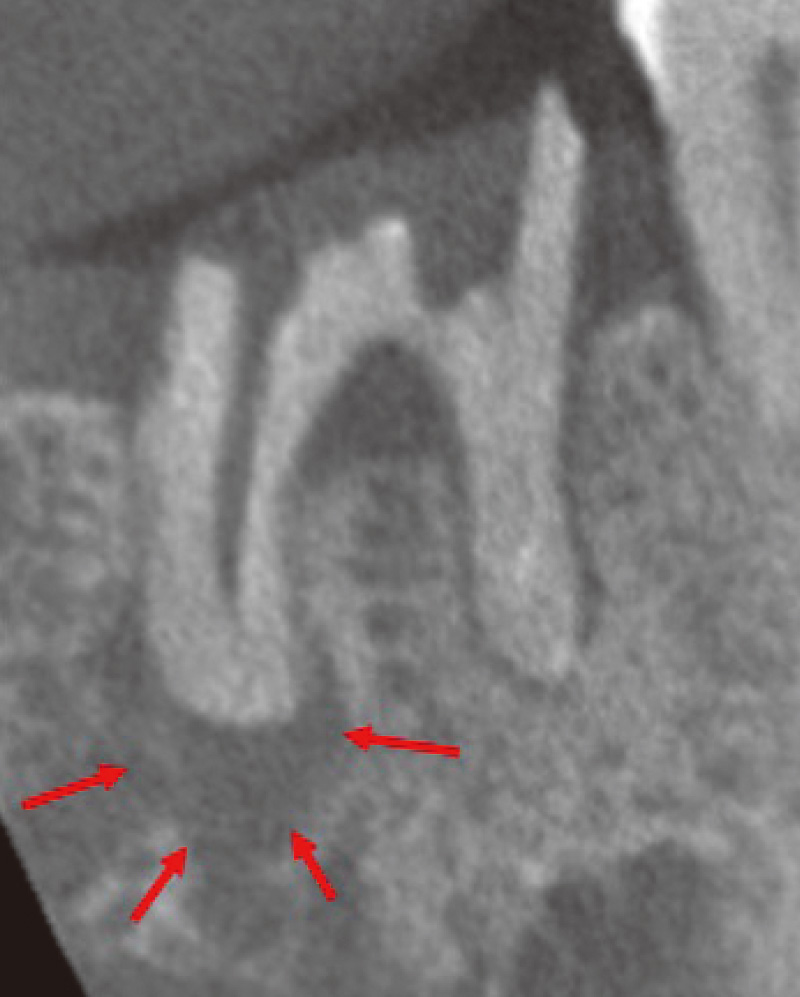

![[写真] CT](/academic/dentalmagazine/wp-content/uploads/sites/2/2025/11/195-3_photo08.jpg)

CTで見ると、近心頰側根も遠心頰側根にも根尖部病変があり、口蓋根は吸収していて、根尖孔が拡大している。この状態になると、根管洗浄を行っても十分細菌が取り切れず、治癒が難しくなる。(Veraviewepocs 3Dfにて撮影) -